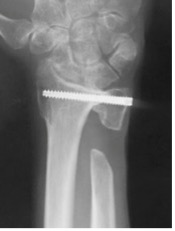

橈骨遠位端骨折に対する鏡視併用手術

橈骨遠位端骨折は頻度の高い骨折の一つで、特に関節内骨折については関節鏡を併用し従来のX線のみでは整復が不十分な関節面の整復を行っています。

術後